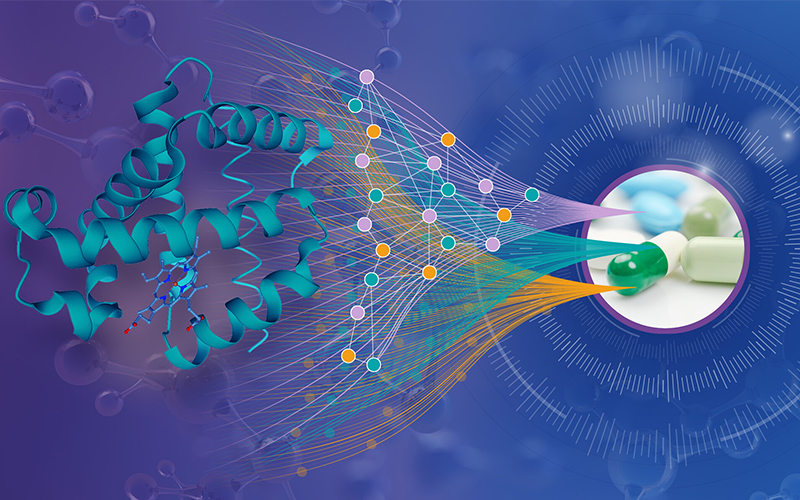

Dive into the science proteins, the remarkable macromolecules that literally build our bodies, and explore the vital roles they play in our lives.